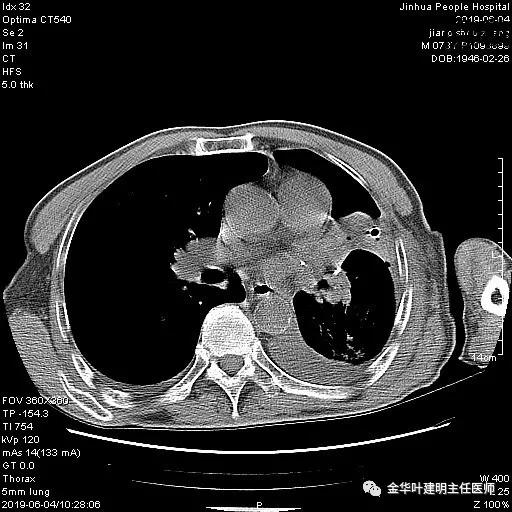

6.4上午:24小时引流出血性乳糜液1800毫升。是否再次手术进行右进胸胸导管结扎,抑或继续保守治疗非常纠结!压力非常大!!多方讨论会诊无法取得一致意见,但一般认为,引流量在1000毫升以上宜积极手术。情况与浙二医院范军强教授联系,请求指导,范教授认为左侧肺手术,损伤胸导管主干的机会较小,多数可保守治疗而愈。在他们的病例中,也有结扎胸导管后引流量仍无减少,效果并不能完全保证。建议可以考虑胸管夹管观察(因为淋巴管压力低,予以适当的压力,漏出量可能会明显减少),同时继续禁食,并静脉营养支持,引流管口可能会有渗液,注意更换敷料。与家属充分沟通后决定试夹管;这天血色素9.0 g/L;胸部CT复查示:

夹管情况下,于6.5复查胸片:

感觉左肺密度还可以,肺没有被全部压萎陷,积液有,但不是特别多。

6.6下午:夹管已2天,生命体征平稳,无显著胸闷气闭症状,试放开胸管,引流出微混血性液650毫升。此时血色素9 g/L;